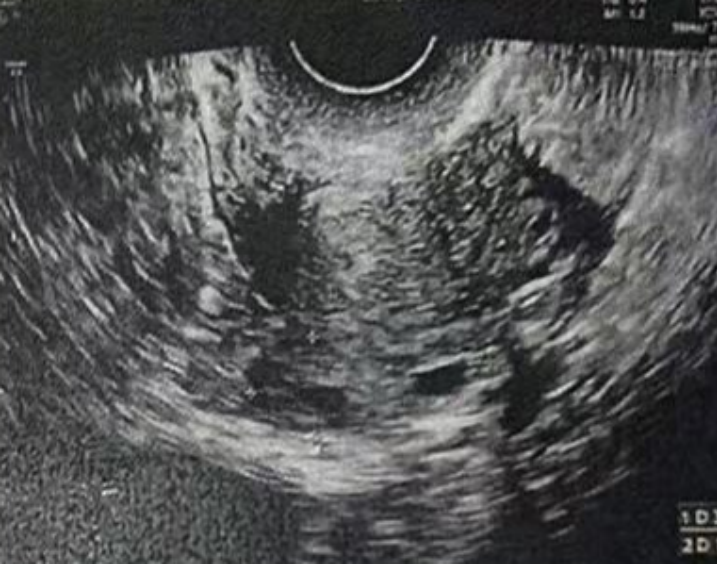

子宫内膜厚度:4.6 毫米,子宫有瘢痕大小 0.76*0.19 厘米

子宫内膜厚度:9.3-10 毫米

- 有粘液滞留在腔内,从峡部瘢痕延伸至子宫底

子宫内膜厚度:8.9 毫米

在进行3毫升的子宫峡部切口冲洗后,经过经腹超声检查显示子宫内膜呈三线状,且子宫腔内未见液体。

• Pre-Irrigation灌洗前: